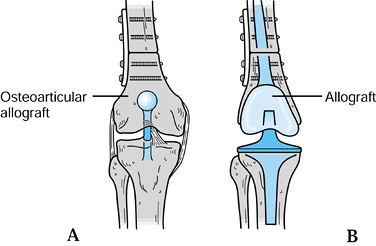

After the tumor has been resected, a properly screened frozen bone

allograft can be placed in the osseous defect. Generally, the same type

of bone that is removed is selected, and the articular cartilage is

removed from the allograft so that the cut surface of the allograft

coapts with the cut surface of the upper tibia (28,142). This creates a large cancellous bone surface for fusion to occur. It is important to fix the allograft rigidly at both ends (Fig. 126.10). This

is accomplished either by a long intramedullary rod from the greater

trochanter to the ankle, supplemented with a compression plate to

prevent rotation, or by an osteosynthesis with two dynamic compression

plates. This graft can be supplemented with a vascularized fibular bone

graft to aid in healing.

Figure 126.9. Intercalary allograft arthrodesis.